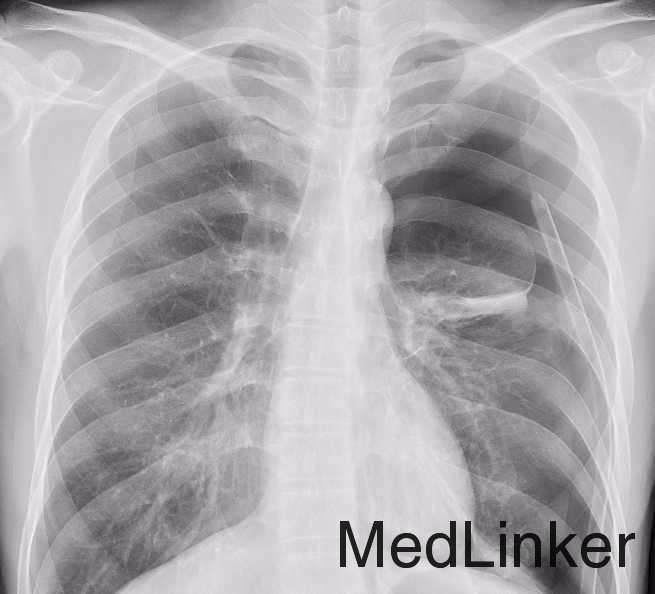

气胸

主诉:突发胸痛3小时。 现病史:患者无明显诱因于今早7:30左右突发胸痛,胸痛剧烈,呼吸困难,就诊于我院急诊,行CT检查提示:左侧气胸,请我科会诊后收入院

胸部CT:左侧肺压缩近80%,纵隔向右移位,左上肺叶与胸壁和纵隔粘连。

气胸 胸腔闭式引流

气胸自愈的可能性有,但是据我观察,不是很多。所以发生气胸之后还是需要紧急性胸腔闭式引流